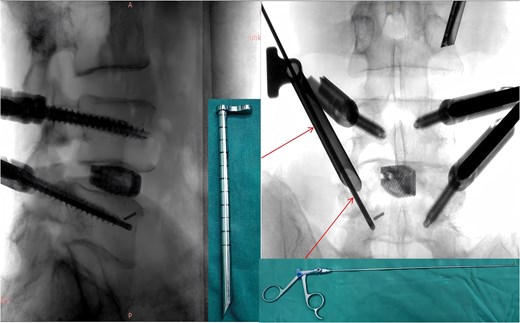

During the surgery, after sufficient decompression at the L4/L5 level and placement of the interbody fusion cage, a complication occurred during the percutaneous pedicle screw insertion. Intraoperative G-arm fluoroscopy confirmed the correct trajectory of the pedicle screw, established by the guidewire and puncture needle, and the pedicle screw was inserted along the established pathway (Fig. 2). However, after removing the guidewire, fluoroscopic imaging revealed that a portion of the guidewire had broken near the anterior margin of the left L5 pedicle screw (Fig. 3). The fracture likely occurred during screw insertion or tightening, which subsequently displaced the broken guidewire toward the anterior vertebral margin. Given the proximity of the fractured guide wire to the anterior vertebral margin, along with the risks of future migration causing injury to adjacent tissues or vessels, as well as the potential for local infection or pain, the decision was made to remove the fractured guidewire after obtaining informed consent from the patient’s legal representative.

Intraoperative fluoroscopic confirmation of guidewire breakage.

Following removal of the left L5 pedicle screw during the procedure, the smallest endoscopic sheath was inserted along with the endoscope to explore the screw trajectory. Under fluoroscopic guidance, endoscopic forcep was utilized to identify and grasp the fractured guidewire (Fig. 4). Tactile feedback of a metallic sensation confirmed precise localization. Approximately 6 mm of the fractured guidewire was successfully extracted (Fig. 5). Subsequent fluoroscopy confirmed complete removal of the broken guidewire. The left L5 pedicle screw was reinserted, and bilateral connecting rods were placed. The nuts were then securely fastened. Hemostasis was confirmed under endoscopic visualization, and the surgical incisions were closed and dressed with sterile coverings.